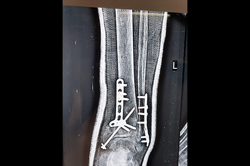

Calcaneum